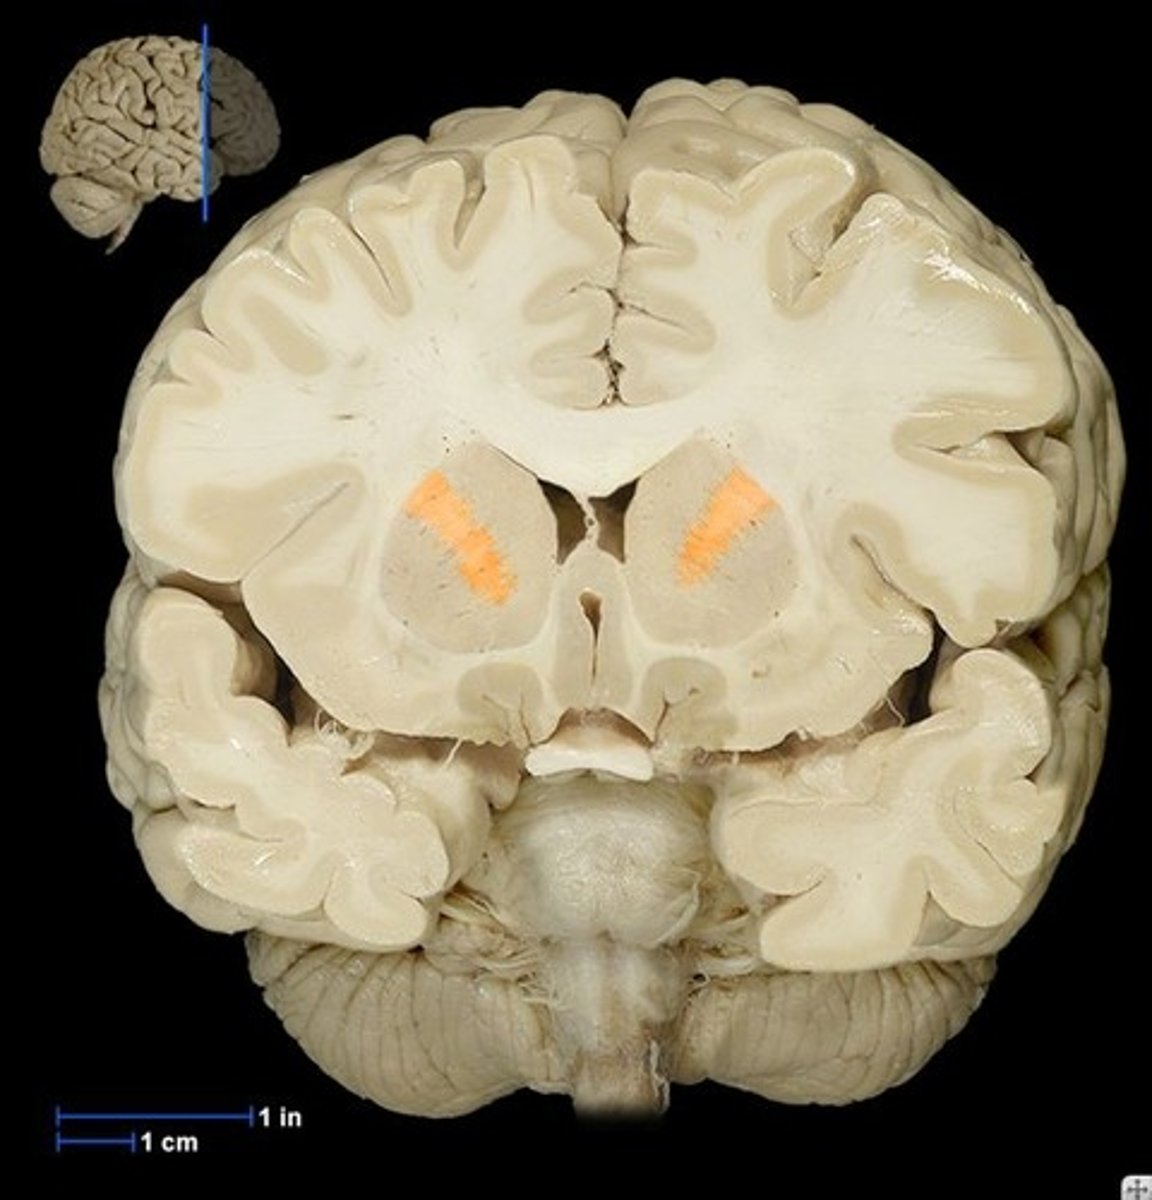

Coronal View